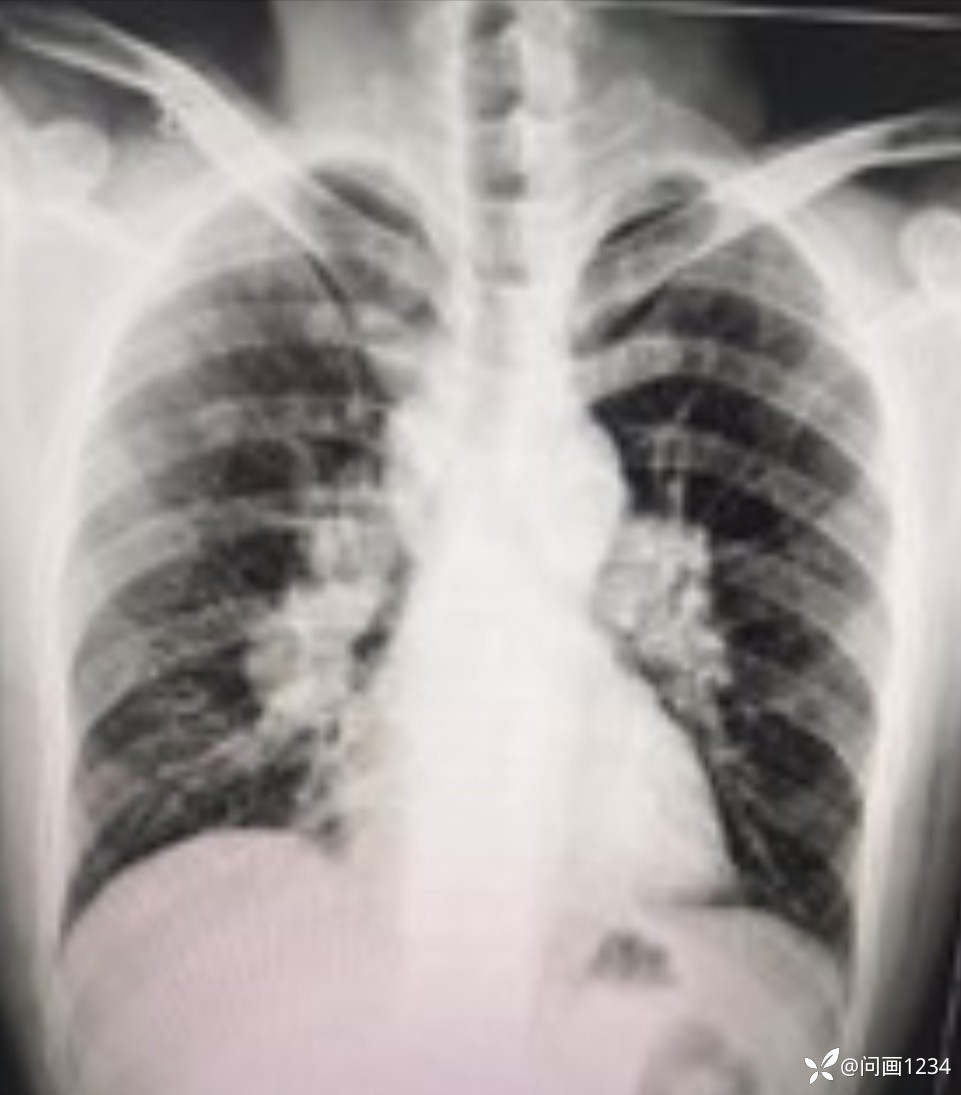

肺结节病误诊一例

男,35岁,咳嗽气紧2个月,各地治疗一直不见好转。DR见双肺门多发肿大的结节影,经了解病人曾在水泥厂工作10年,于是考虑尘肺病不排除淋巴转移瘤,建议病人上大医院确诊。半年后病人再次找到我,说经三甲医院最后诊断为:肺结节病。现程主任征集肺部影像病例,特为影像医生分享此病例。